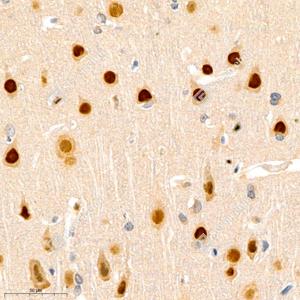

IHC检测SATB2蛋白(货号 GB111449). 样品: 大鼠脑, 4%多聚甲醛 (货号G1101) 固定12-24小时. 抗原修复: 柠檬酸抗原修复液(干粉, pH 6.0) (G1201), 98℃, 20分钟. —抗: 1: 1500稀释, 4℃ 孵育过夜. 二抗: HRP标记山羊抗兔IgG (H+L) (货号GB23303), 1: 200稀释, 室温孵育1小时. |